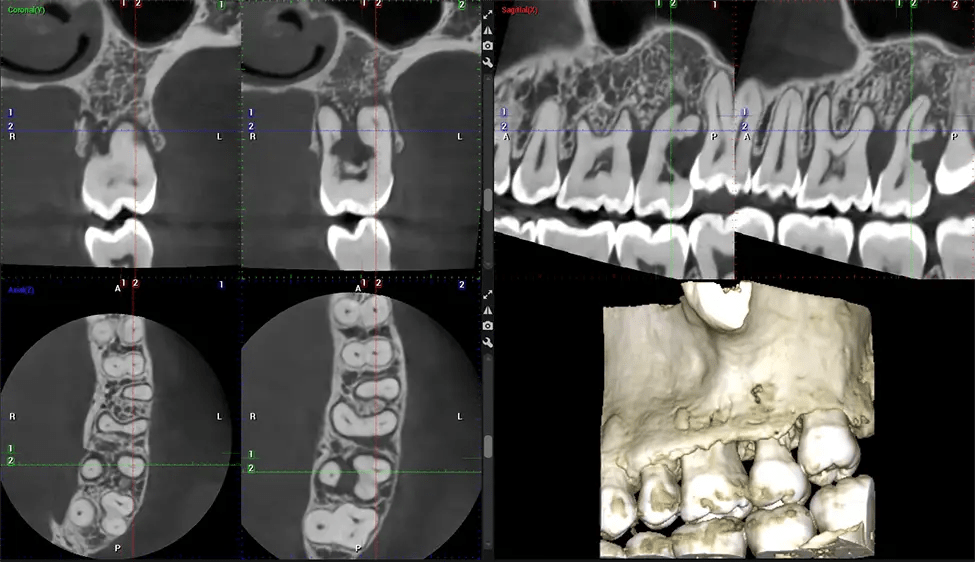

Cone Beam Computed Tomography (CBCT) is an advanced imaging technique used in dentistry and maxillofacial surgery to obtain detailed 3D images of the oral and maxillofacial structures. At Dr G Dental Studio, our CBCT scanners utilize a cone-shaped X-ray beam and a specialized detector to capture images from different angles. A computer then combines these images to create a 3D representation of the patient’s oral anatomy.

This 3D scan, called cone beam computed tomography, gives your dentist a more complete image of your oral anatomy and disease processes than a traditional X-ray. Unlike conventional X-rays, which capture a 2D image of your mouth from various angles, a 3D scan takes multiple digital X-rays for one image. It provides a complete view of your jaw, teeth, nerves, and soft tissues. This enhanced view allows dentists to detect minor issues not visible in traditional 2D scans, such as impacted wisdom teeth or bone fractures in the sinus cavity.

After the scanning process, the captured X-ray images are processed by the CBCT software, which applies algorithms to reconstruct a detailed 3D image of the scanned area. The software compiles these individual X-ray images and creates a digital 3D representation of the patient’s anatomy. The reconstructed 3D CBCT image can be viewed and analyzed by the dentist or radiologist. This image can be manipulated, rotated, and zoomed in or out to examine specific structures and evaluate the patient’s condition.

Planmeca Viso G7 CBCT ( Cone Beam CT Scan ) is designed to surpass the demands of industry leaders, specialists, and large institutions. It’s has a large ø25×30 cm sensor with four built-in cameras. It can capture unlimited volume sizes from a ø3×3 cm to a ø30x30cm volume capturing the skullcap through C7 on the cervical spine. The Planmeca Viso G7 offers the industry’s largest single volume scan of ø30×19 cm. It’s poised to handle advanced imaging modalities such as Planmeca ProFace® and Planmeca 4D™ Jaw Motion technology. The occipital head support allows an unimpeded view of facial tissue.

Our patented SCARA technology enables doctors to capture True Extraoral Bitewings that are as accurate at detecting caries as a 2D bitewing series, but with half the radiation dose. With our bitewings, doctors can view the apices of teeth on both jaws providing a more comprehensive view of the patients’ anatomy.